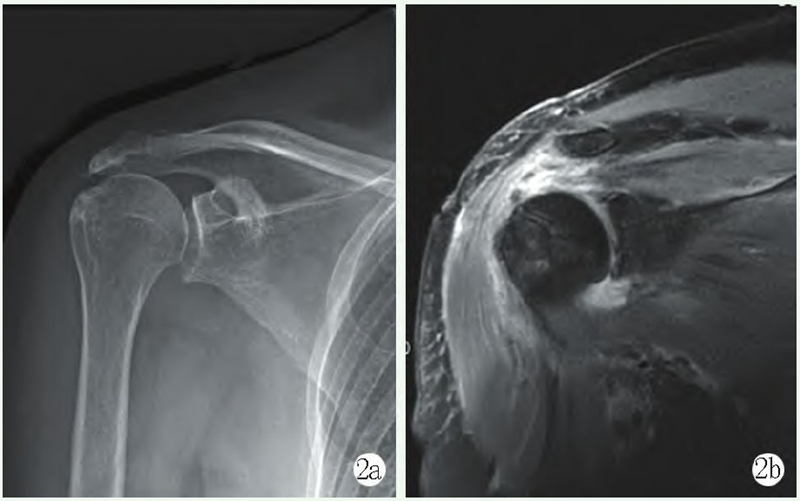

影像学检查:X线片示肩峰外缘增生,肱骨头上移,肩峰-肱骨距离短缩,肱骨后方Hill-Sachs损伤。MRI示:右侧前下盂唇损伤,右侧肱骨后方Hill-Sachs损伤。右冈上肌全层撕裂并回缩,轻度脂肪浸润(图3a~3c)。

图3a: 术前MRI显示右侧前下盂唇损伤;3b: 术前MRI显示右侧肱骨后方Hill-Sachs损伤;3c: 术前MRI显示右冈上肌全层撕裂并回缩,轻度脂肪浸润